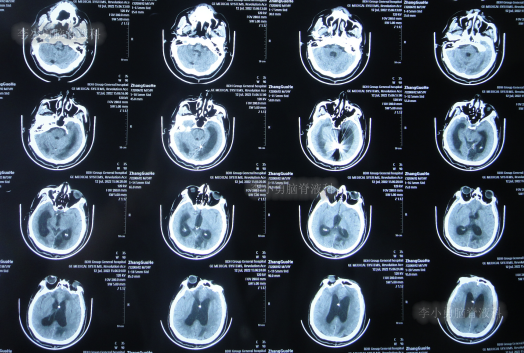

患者于2022年3月16日早晨起床后,无诱因突发头痛,恶心及呕吐,嗜睡,急就诊于当地黑龙江省海伦市某医院,查头颅CT扫描脑出血(片子丢失),因技术有限,120急救车转至上级的黑龙江省哈尔滨某三甲医院,再次复查头颅CT示出血量无明显增多(片子丢失),当天给予脑室外引流术,脑室外引流术后次日查头颅CT示脑出血脑室引流术后(图-1),医生考虑为动脉瘤出血。

图-1:2022年3月17日头颅CT

2022年3月23日(脑动脉瘤栓塞术后5天),查头颅CT示积血减少(图-3);术后身体恢复良好,能自行下地活动。

图-3:2022年3月23日头颅CT

2022年4月27日(入院治疗3天),脑脊液培养出细菌,给予抗感染治疗,查头颅CT示脑室扩张加重(图-5)。

图-5:2022年4月27日头颅CT

抗感染治疗28天即2022年5月25日,查头颅CT示仍脑积水(图-6),脑脊液仍有细菌。

图-6:2022年5月25日头颅CT

抗感染治疗41天即2022年6月7日,脑脊液化验细菌消失,但查头颅CT示仍脑积水(图-7)。

图-7:2022年6月7日头颅CT

2022年6月13日(脑室腹腔分流术后5天),术后患者仍走路不稳,有时胡言乱语,言语不清,小便失禁,查头颅CT(图-8)示脑室仍有扩张。

图-8:2022年6月13日头颅CT

2022年6月17日(分流术后9天即第2次该院治疗53天),查头颅CT虽仍有脑积水(图-9),但仍让患者出院,出院时:仍走路不稳,有时胡言乱语,言语不清,小便失禁;转至当地的某医院进行治疗。

图-9:2022年6月17日头颅CT

在当地的某医院进行康复治疗1个月的时间,患者症状无改善,期间3次查头颅CT(图-10、图-11、图-12)均示仍脑积水。

图-10:2022年6月20日头颅CT

图-11:2022年7月1日头颅CT

图-12:2022年7月12日头颅CT